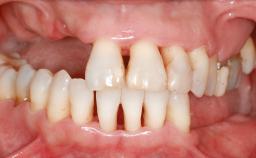

A 45-year-old woman with a completely edentulous maxilla was referred to evaluate the possibility of rehabilitation with an implant-supported prosthesis. This patient was healthy and a non-smoker. She had been wearing a maxillary complete denture opposing a natural mandibular dentition since her twenties. This situation had resulted in progressive resorption of the alveolar ridge, repeatedly creating a need for relining the denture. Twenty years later, despite multiple adaptations and the use of “glues” the denture was unstable and causing the patient psychological and functional discomfort.